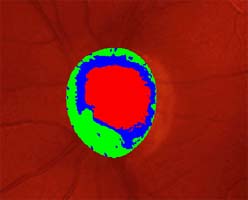

Modrá šipka - ukazuje plochu na sítnici, která obsahuje nervová vlákna. Sítnice je jemně proužkovaná, světlejší, cévy "jsou jako pod závojem". Červená šipka - ukazuje místo bez nervových vláken. Sítnice je tmavší, bez proužkování. Cévy jsou ohraničeny neobvykle ostře.